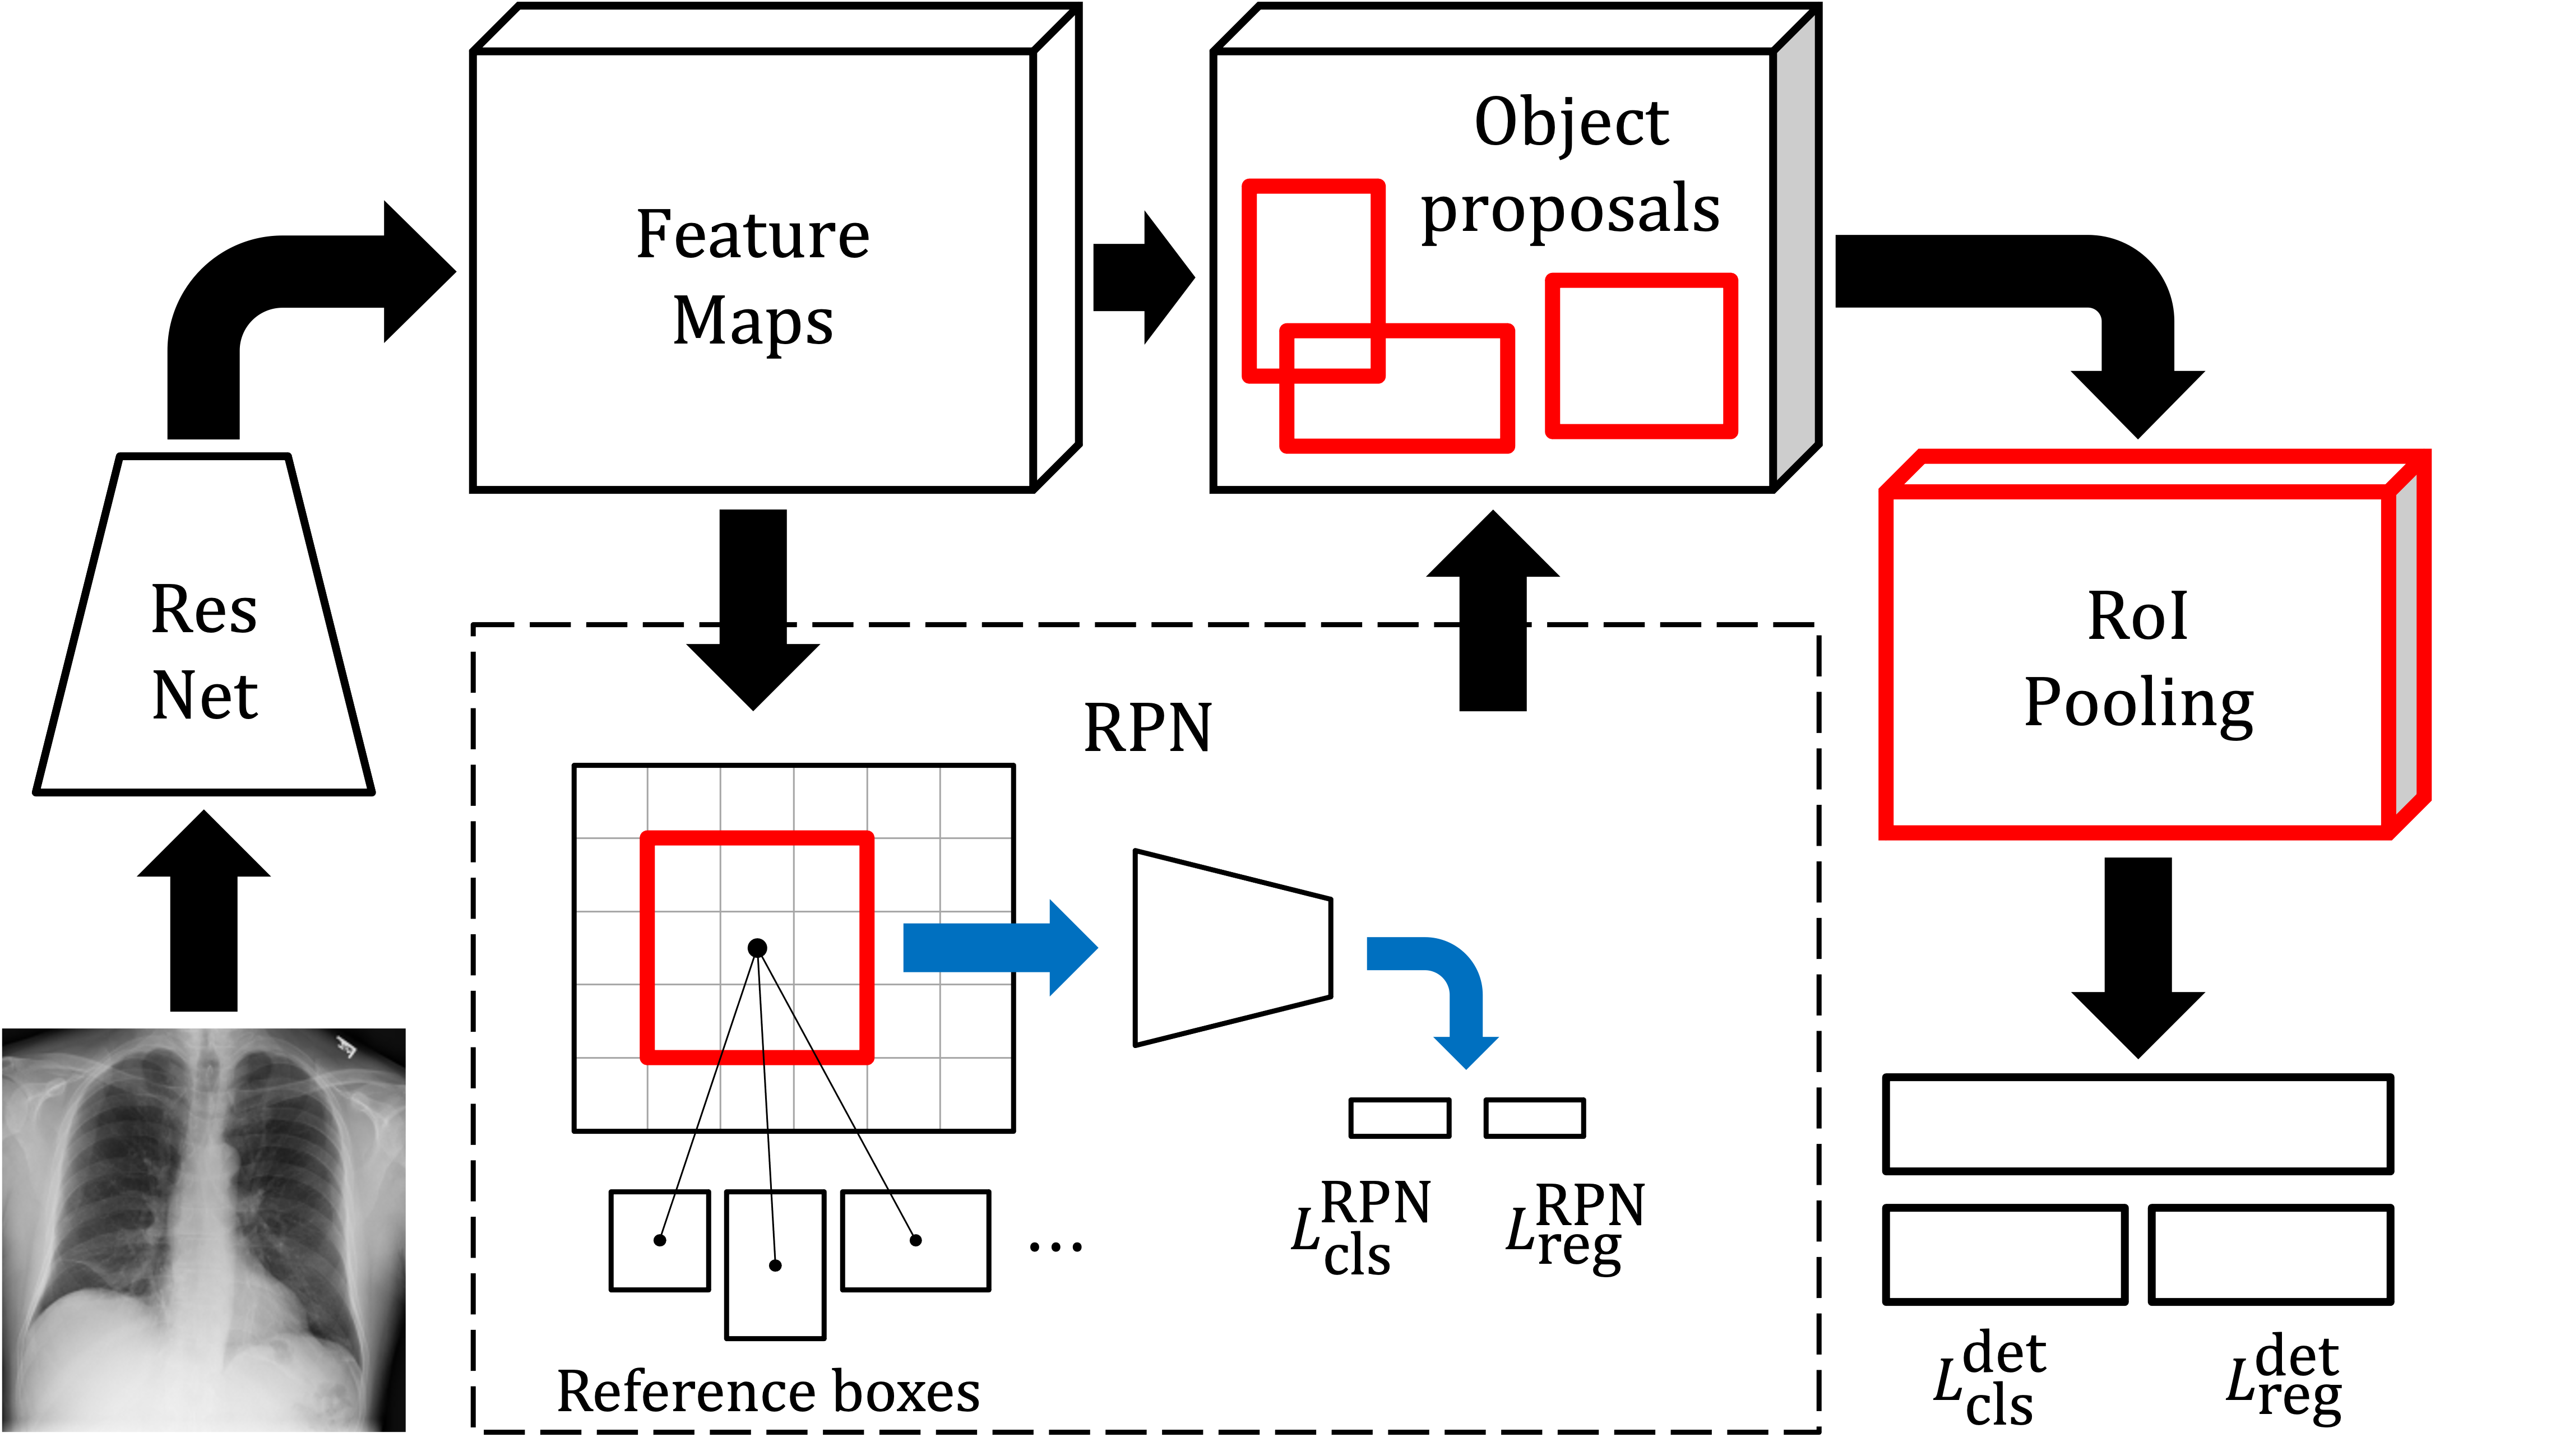

For multi-label classification, we adapt Faster R-CNN (Ren et al., 2016) outlined in Figure 2 and described below. Faster R-CNN uses a region proposal network (RPN) to generate region proposals which are fed to a detection network for classification and bounding box regression. This way of solving the task in subsequent steps has similarities with our two-stage algorithm although Faster R-CNN can be trained end-to-end. We make small modifications to the training procedure of the original model in the end of this section.

The RPN generates region proposals relative to a fixed number of reference boxes—anchors—centered at the locations of a sliding window moving over convolutional feature maps. Each anchor is assigned a binary label based on its overlap with ground-truth bounding boxes; positive anchors are also associated with a ground-truth box with location . The RPN loss for a single anchor is

| (3) |

where represents the refined location of the anchor and is the estimated probability that the anchor contains an object. The binary cross-entropy loss and a smooth loss are used for the classification loss and the regression loss , respectively. For a mini-batch of images, the total RPN loss is computed based on a subset of all anchors, sampled to have a ratio of up to 1:1 between positive and negative ditto.

A filtered set of region proposals are projected onto the convolutional feature maps. For each proposal, the detection network—Fast R-CNN Girshick (2015)—outputs a probability and a predicted bounding box location for each class . Let , where , is the number of classes and represents a catch-all background class. For a single proposal with ground-truth coordinates and multi-class label , the detection loss is

| (4) |

where and is a smooth loss. To obtain a probability vector for the entire image, we maximize, for each class , over the probabilities of all proposals.

During training, Faster R-CNN requires that all input images come with at least one ground-truth annotation (bounding box) and its corresponding label . To increase sample-efficiency, we enable training the model using non-annotated but labeled samples from the source domain and annotated but unlabeled samples from the target domain. In the RPN, no labels are needed, and we simply ignore anchors from non-annotated images when sampling anchors for the loss computation. For the computation of (4), we handle the two cases separately. We assign the label to all ground-truth annotations from the target domain and multiply by the indicator . For non-annotated samples from the source domain, there are no box-specific coordinates or labels but only the labels for the entire image. In this case, (4) is undefined and we instead compute the binary cross-entropy loss between binarized labels and the probability vector for the entire image.

We train the RPN and the detection network jointly as described in Ren et al. (2016). To extract feature maps, we use a Feature Pyramid Network Lin et al. (2017) on top of a ResNet-50 architecture He et al. (2016). We use the modfied model—DALUPI-E2E—in the experiments in Section 5.2 and 5.3. Note that we may also train the model in a LUPI setting, where no information from the target domain is used, in which case we call it LUPI-E2E.